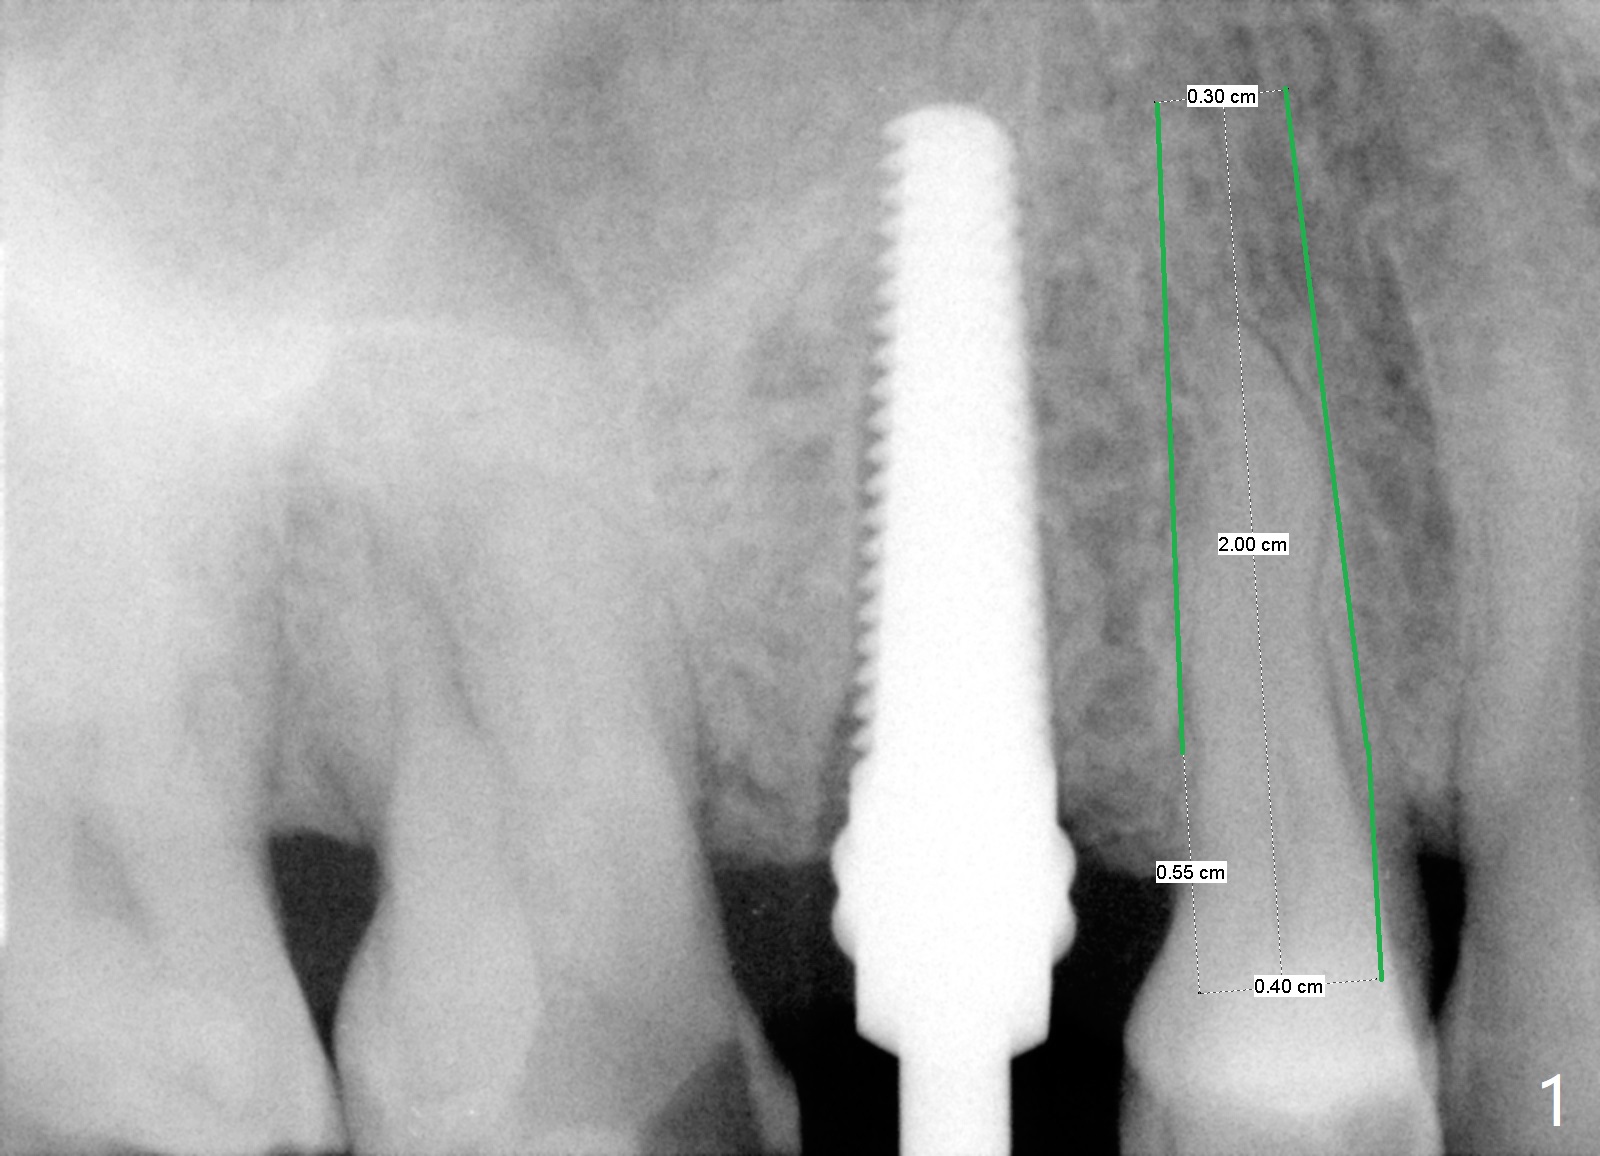

A 78-year-old man with diabetes and recent history of stroke wants to have an implant at #5 (fracture). He was not pleased with the long implant at #4 several years ago with delayed healing. This time he requests a short implant instead (Fig.1,2). Make sure that he has stopped Aspirin.